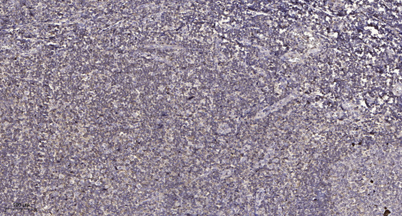

Product name: Mnk1 rabbit pAb

Dilutions: Western Blot: 1/500 - 1/2000. Immunohistochemistry: 1/100 - 1/300. ELISA: 1/20000. Not yet tested in other applications.

Immunogen: The antiserum was produced against synthesized peptide derived from human MKNK1. AA range:111-160

Observed Band: 51kD

Background: MAP kinase interacting serine/threonine kinase 1(MKNK1) Homo sapiens This gene encodes a Ser/Thr protein kinase that interacts with, and is activated by ERK1 and p38 mitogen-activated protein kinases, and thus may play a role in the response to environmental stress and cytokines. This kinase may also regulate transcription by phosphorylating eIF4E via interaction with the C-terminal region of eIF4G. Alternatively spliced transcript variants have been noted for this gene. [provided by RefSeq, Jan 2012],